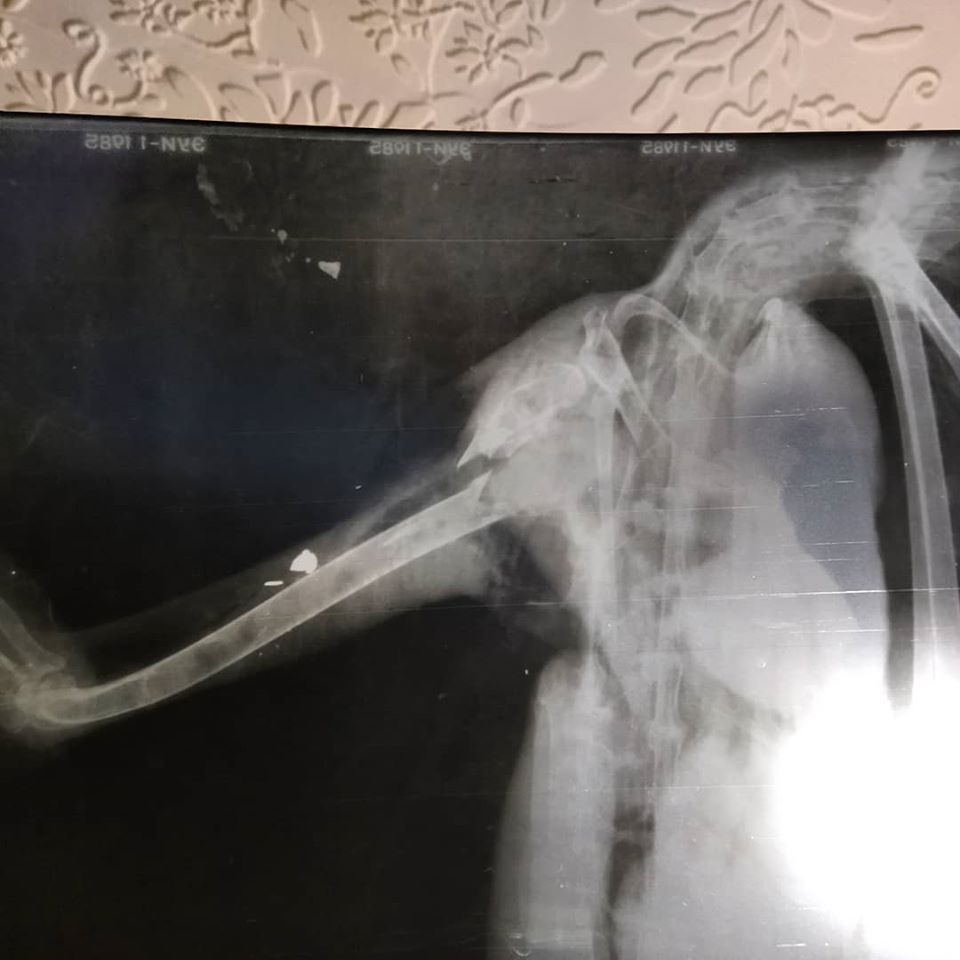

В приют поступила цапля с огнестрельным ранением.

В Днепре в приюте для диких животных «Пегас» спасают белую цаплю. Подстреленную птицу привезли из города Горишние Плавни Полтавской области. До этого ей оказывали помощь местные ветеринары.

Известно, что в раненую цаплю стреляли. Птица получила открытый перелом крыла, из-за чего в нем отсутствует кровообращение. Пострадавшую конечность теперь придется ампутировать. Сейчас пернатую пациентку готовят к операции.